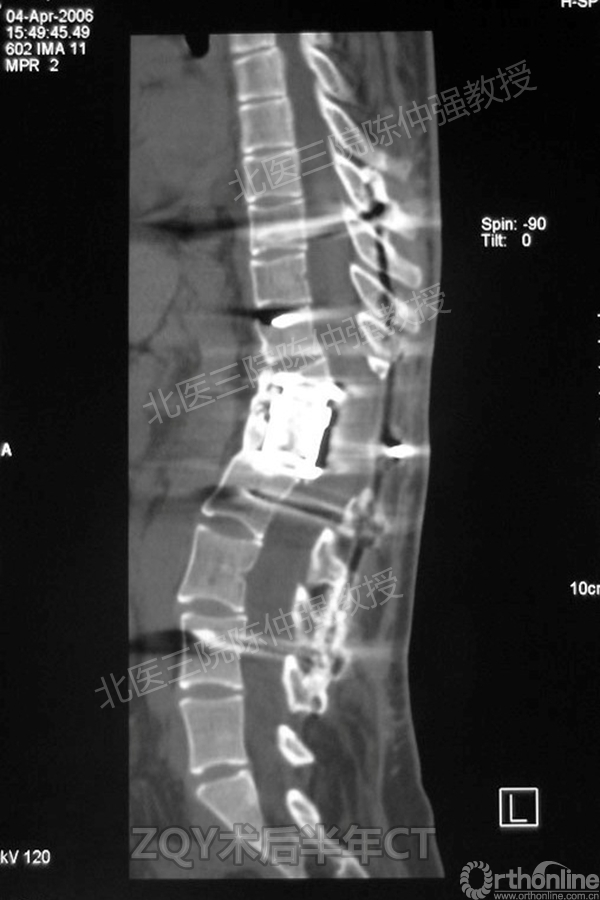

2005年,陈仲强教授在AOSpine年会上分享了一例胸腰椎陈旧结核性侧后凸畸形病例。资料如下:

ZQY术后半年

患者女性17岁,胸腰椎陈旧结核性侧后凸畸形,局部呈“麻花状”扭转,无神经功能受损表现。2005年,陈仲强教授带领团队实施后路+侧前方联合入路脊柱节段切除、双轴旋转矫形术。术后患者外观显著改善,神经功能正常。术后随访证实患者截骨矫形节段骨性融合良好,矫形效果持续良好。